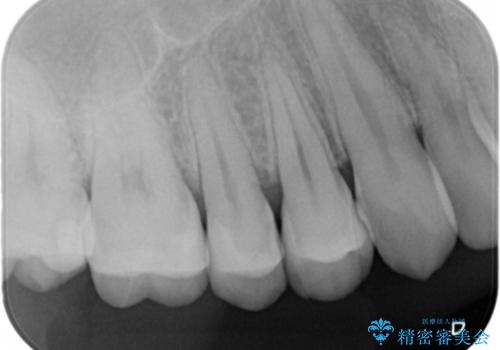

- 銀の詰め物を白くしたいとの事で来院。

拡大鏡下で詰め物を外しう蝕がないことを確認して、e-maxインレーにて治療しました。

白い詰め物が入り大変満足して頂けました。